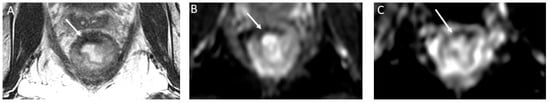

- nCR serves as a transitional state between CR and other responses, with substantial regression evident. Of note, the term nCR emerged only recently, driven by the observation that a significant proportion of patients who display very good yet incomplete responses during the first assessment do ultimately achieve a CR when provided with a longer interval before re-assessment (26) (Figure 3). nCR retains a trace of diffusion restriction post-neoadjuvant therapy, underscoring ongoing positive changes. In cases where tumor signal or diffusion restriction persists after one or two short-term follow-up evaluations, the case should be reclassified as iCR and considered unsuitable for observation.